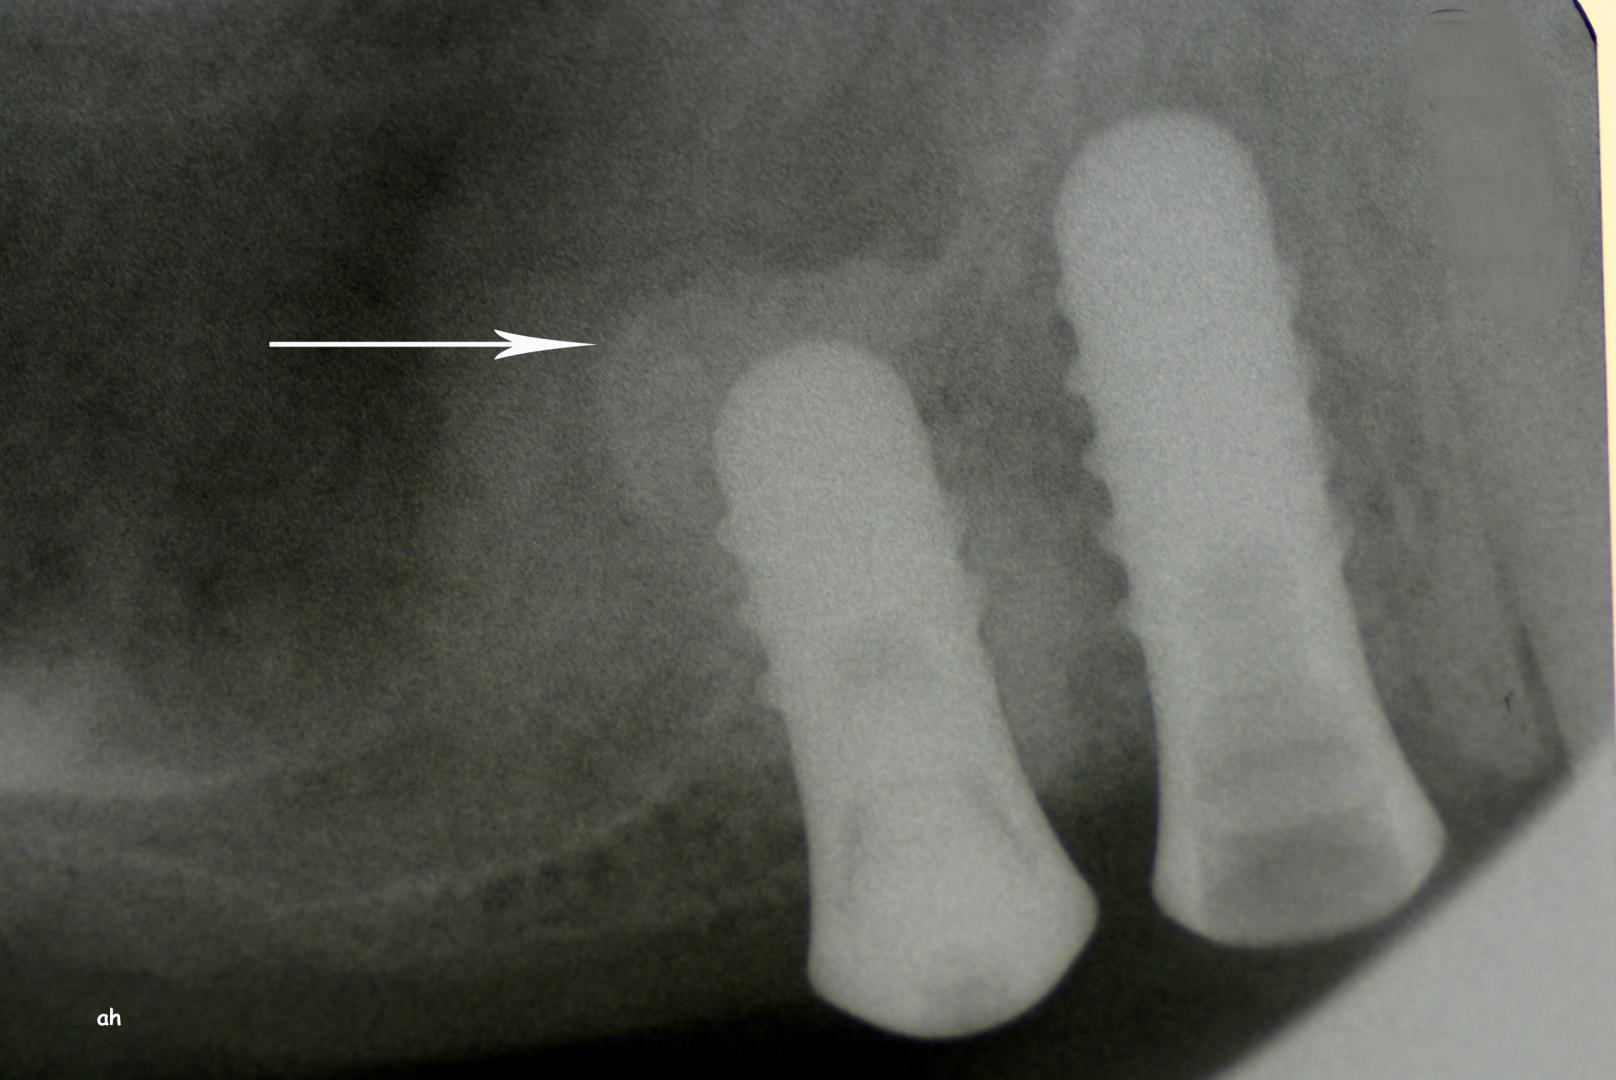

Exemple 12: Ici la pose de deux implants est envisagée, mais la hauteur d'os est insuffisante pour le deuxième implant. Le sinus (qui est une cavité creuse) est à moins de 6 mm de la surface de l'os. Idéalement il faudrait 10 mm d'os.

Exemple 12: Il faut donc relevé le sinus avec une greffe d'os avant de poser l'implant (Sinus lift).

Exemple 14: Il est prévu de mettre un implant entre la molaire et prémolaire, mais le sinus se trouve à moins de 4 mm de la surface. Il faut donc relever le sinus avec une greffe d'os